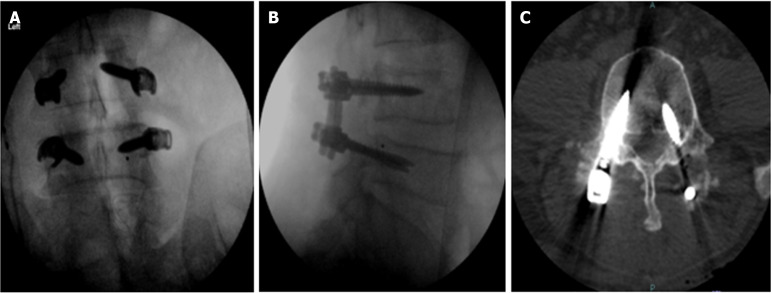

Abstract Image